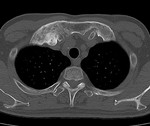

[画像診断]膿胸関連悪性リンパ腫、画像所見について 2011-04-26